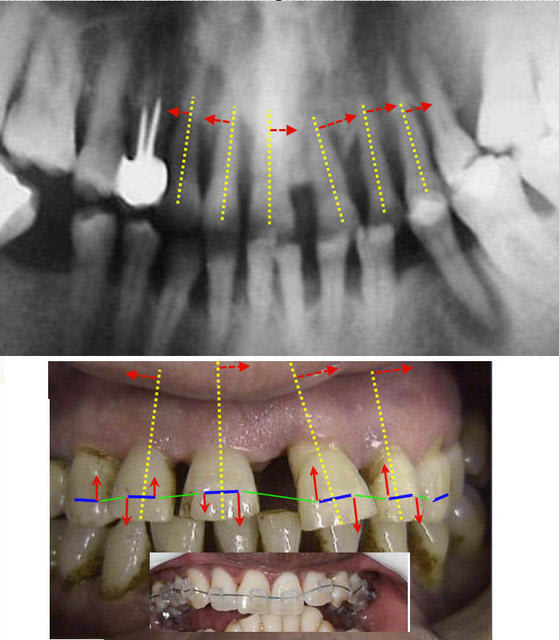

Observez maintenant celles qui sont engendrées par une mécanique reposant sur l'utilisation de braquets traditionnels (planche jointe)

Tout décalage vertical entre deux dents induira automatiquement une force latérale à l’apex.

Que pensez-vous qu’on puisse faire pour la rendre négligeable ?